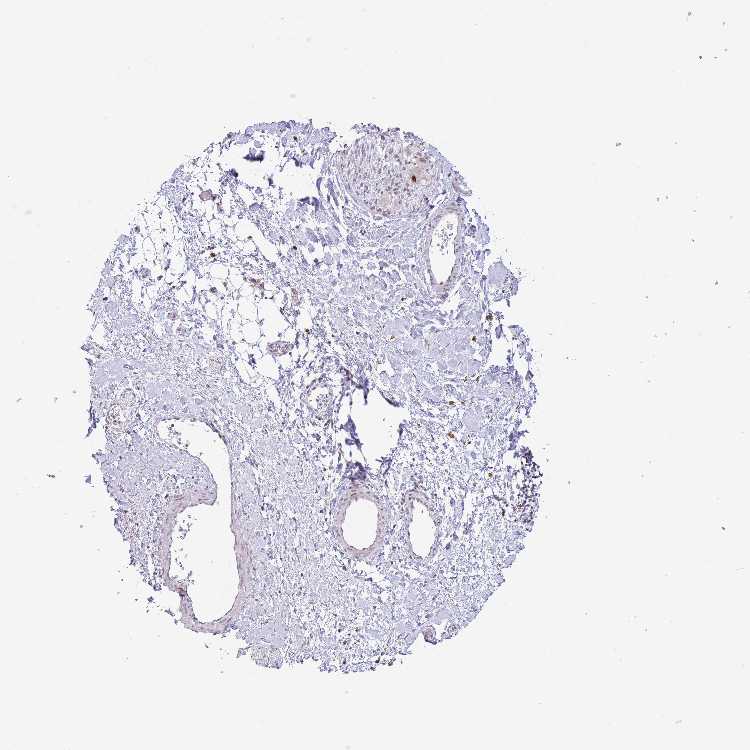

SOFT TISSUE 1 - Antibody stainingi

Antibody staining in the annotated cell types in the current human tissue is reported as not detected, low, medium, or high, based on conventional immunohistochemistry profiling in selected tissues. This score is based on the combination of the staining intensity and fraction of stained cells.

Each image is clickable and will lead to virtual microscopy that enables deeper exploration of all samples and also displays staining intensity scores, fraction scores and subcellular localization as well as patient and tissue information for each sample.

Antibody HPA049060

Fibroblasts Not detected

Peripheral nerve Medium

SOFT TISSUE 2 - Antibody stainingi